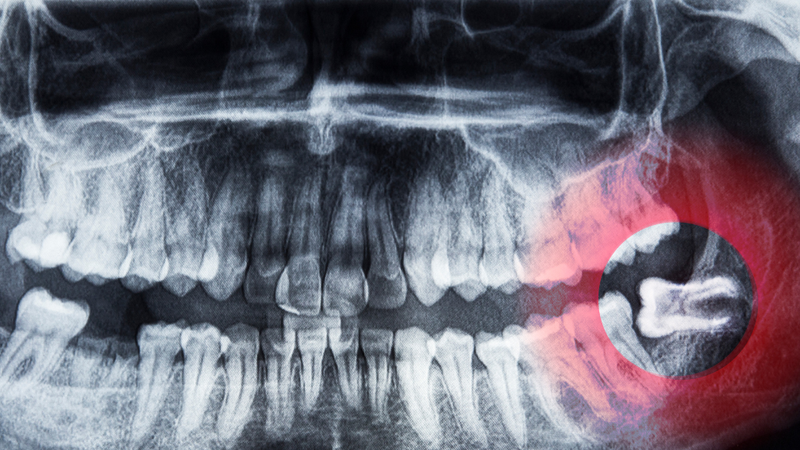

Răng khôn, hay còn gọi là răng số 8, là những chiếc răng cuối cùng mọc trong hàm và thường xuất hiện ở độ tuổi từ 17 - 25. Tuy nhiên, do không gian trong hàm thường không đủ để răng khôn mọc đúng vị trí, nên răng khôn thường mọc lệch, mọc ngầm hoặc bị kẹt dưới lợi.

Khi răng khôn mọc lệch, nó có thể đẩy các răng khác xung quanh, gây ra sự xô lệch của toàn bộ hàm răng. Điều này không chỉ tạo ra sự bất tiện trong việc vệ sinh răng miệng mà còn dẫn đến đau nhức, khó chịu ở vùng hàm, gây ra những vấn đề nghiêm trọng về khớp cắn và cấu trúc hàm.